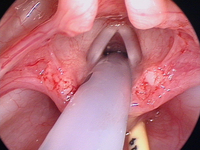

Laryngomalacia

Typical example of laryngomalacia

From the personal teaching collection of Simone J. Boardman, MBBS, FRACS (OHNS) and C. Martin Bailey, BSc, FRCS, FRCSEd